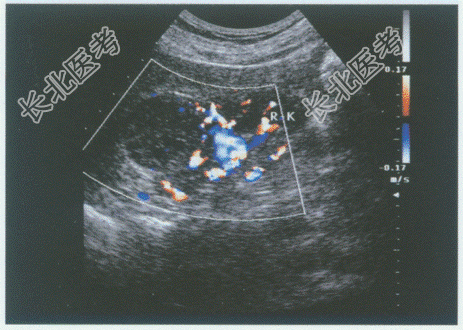

- 单项选择题临床资料:女, 52岁,自述无痛性肉眼血尿3天。

化验检查: 尿常规红细胞满视野。

超声综合描述:右肾上极可见4.3cm×3.7cm低回声区, 边界清晰,形态规则, 向包膜外突起,CDFI: 低回声区周边可见丰富动静脉血流信号。见下图及彩图。